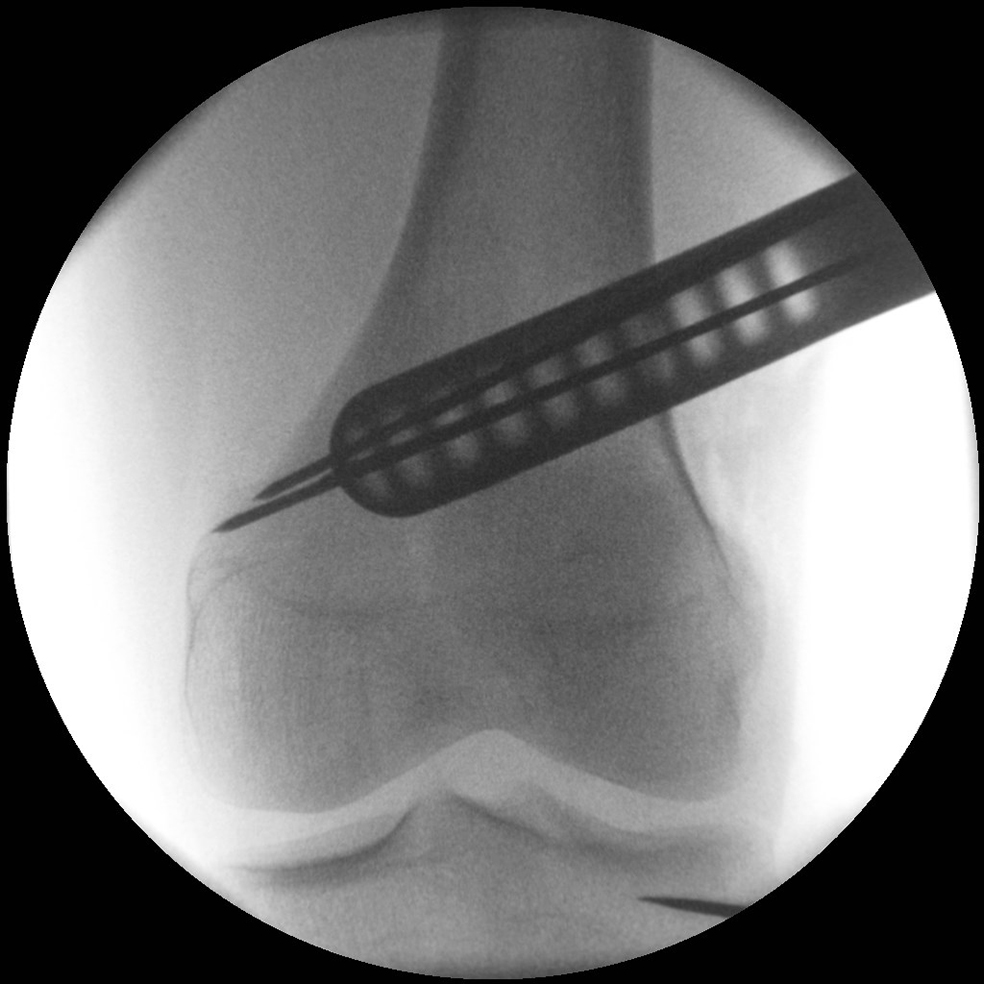

Following completion of the DFO and fixation with the TomoFix MDF Anatomical (Fig 10) the new aiming arm and K-wire guide system was used for the open wedge HTO.

After performing a minimally invasive approach at the medial proximal tibia, the first step of the new K-wire guiding system is definition of the hinge point with a K-wire from the lateral aspect (Fig 11). The guiding arm for the osteotomy was then inserted with the radiolucent hook in situ (Fig 12). The guiding arm should be adjusted under intensifier control and finally fixed with a K-wire. At this stage two K-wires for the osteotomy can be inserted and the guiding arm can be removed. The saw guide is then mounted and guides the sawblade safely (Fig 13 and 14).